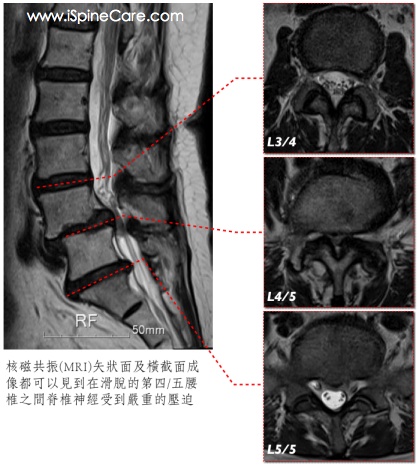

椎間滑脫和因而增生的脊椎骨刺都可能造成脊椎神經根和坐骨神經的壓迫,在施行手術治療之前,必須有核磁共振(MRI)檢查來評估脊椎神經壓迫的嚴重度,並排除有其他病因(如腫瘤或感染等)的可能性。另外,微創脊椎手術的手術傷口相當小,若沒有精準的定位,就不容易找到真正的病灶,手術時就可能忽略了某些部位而影響手術治療的效果。